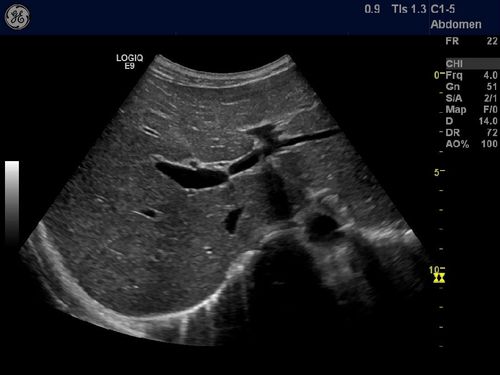

第一肝门超声图

第一肝门超声图,超声第一肝门切面图

一,超声在肋下斜切显示第一肝门过程中,会发现门静脉左支在左肝内呈"

肝内实性结节,高回声,占位,血管瘤,小结节 剑突下斜切,第一肝门,正常

超声第一肝门切面图

超声第一肝门

第一肝门超声手法图解

第一肝门解剖图超声图

肝脏第一肝门超声图像

第一肝门超声图飞鸟征